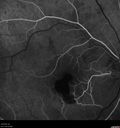

Perifoveal Microaneurysm - Not Diabetic (also reticular pseudodrusen)365 views87 year old female with fluctuating macular edema in the right eye from a perifoveal MA. (no treatment). VA 20/40 OUApr 02, 2020